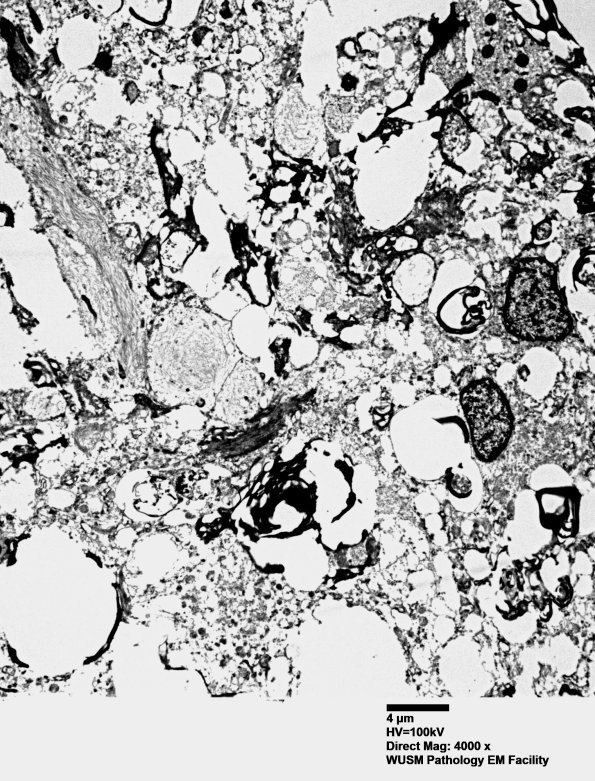

Washington University Experience | MYELIN (IMMUNE-MEDIATED) | Inflammatory Demyelination | 15K3 Case 15 EM 027A2 - Copy

In some areas there is residual myelin debris. (electron micrograph)